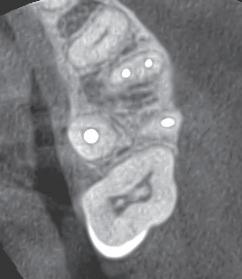

August 2023: Biopsy performed from right lower lip and surgeon described the areas as erythroleukoplakias. The biopsy diagnosis was hyperkeratosis, acanthosis with acute and chronic inflammation. A special stain for fungal organisms (candida) was performed and was negative. This initial biopsy specimen was not evaluated by OU Oral Pathology Lab at this time.

October 2023: His general dentist notes the persistence of the lesion and refers the patient to OU Oral Pathology.

November 2023: Evaluation by oral pathologist and recommendation for certain tests to be ran by primary care physician to rule out a certain infectious disease.

The diagnosis of syphilis can be somewhat challenging due to several factors. The Venereal Disease and Research Laboratory (VDRL) and rapid plasma regain (RPR) can test negative for several weeks following initial infection. This is due to delay in antibody production by the patient. However, after 6 weeks this can be a reliable test and recommended - but beware of early false negatives early in the disease process. Biopsy and dark-field examination on a smear can be challenging to confirm infection with Treponema pallidum since other treponema organisms can be isolated from the oral cavity. However, these latter methods could be most helpful in making the earliest possible diagnosis due to the delay in antibody production for serologic studies. There is a specific immunohistochemical marker for T. pallidum which can be helpful to make an early diagnosis if suspicious for the infection. Serologic testing remains the gold standard for diagnosis.